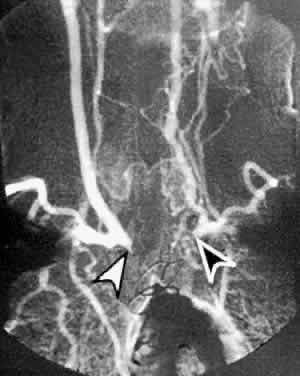

CAROTID ANGIOGRAPHY

Carotid angiography is performed by selective common carotid arterial injection of a radiopaque contrast dye via transfemoral catheterization. In the traditional technique, the image of the inner luminal silhouette is produced on x-ray emulsion (Fig. 10A and B). More recently, digital images and computerized image enhancement have improved resolution and reduced the amount of contrast dye required.46,47 This method can detect ulcerative lesions, severe stenosis, and formation of mural thrombus. It can also demonstrate collateral circulatory patterns.

Fig. 10. A. Digital subtraction aortogram revealing a 90% atherosclerotic stenosis of the proximal left common carotid artery (black arrowhead) and 80% stenosis of the proximal left subclavian artery (white arrowhead). RSCA, right subclavian artery; RCCA, right common carotid artery; RVA, right vertebral artery; LCCA, left common carotid artery; LSCA, left subclavian artery. B. Digital subtraction angiogram with a right common carotid injection from the same patient. There is complete occlusion of the right internal carotid artery due to atherosclerosis (white arrowhead). The right external carotid artery (RECA) and the right common carotid artery (RCCA) fill normally.

The most serious complications of carotid angiography are aortic or carotid artery dissection, embolic stroke, and myocardial infarction.48 Other complications include dye reactions, renal injury, hematoma, pseudoaneurysm, and arterial thrombosis. Carotid angiography carries a 1% risk of morbidity and 0.06% risk of mortality. As with all tests, the advantages of selective carotid angiography must be weighed against the possible risks.

Despite its expense and low but definite morbidity rate, carotid angiography remains the most reliable method of assessing atherosclerotic carotid disease,38 and it serves as the “gold standard” in the evaluation of all other tests of the carotid arteries.